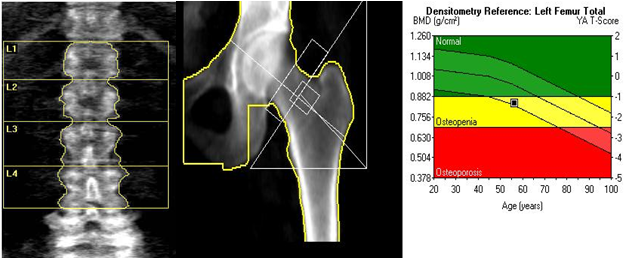

골밀도 검사 결과는 일반적으로 T-score라는 지표를 통해 판단합니다. T-score는 건강한 젊은 성인의 평균 골밀도와 비교하여 현재 골밀도 상태를 평가하는 지표입니다.

T-score 기준은 다음과 같습니다.

- -1.0 이상 : 정상

- -1.0 ~ -2.5 : 골감소증

- -2.5 이하 : 골다공증